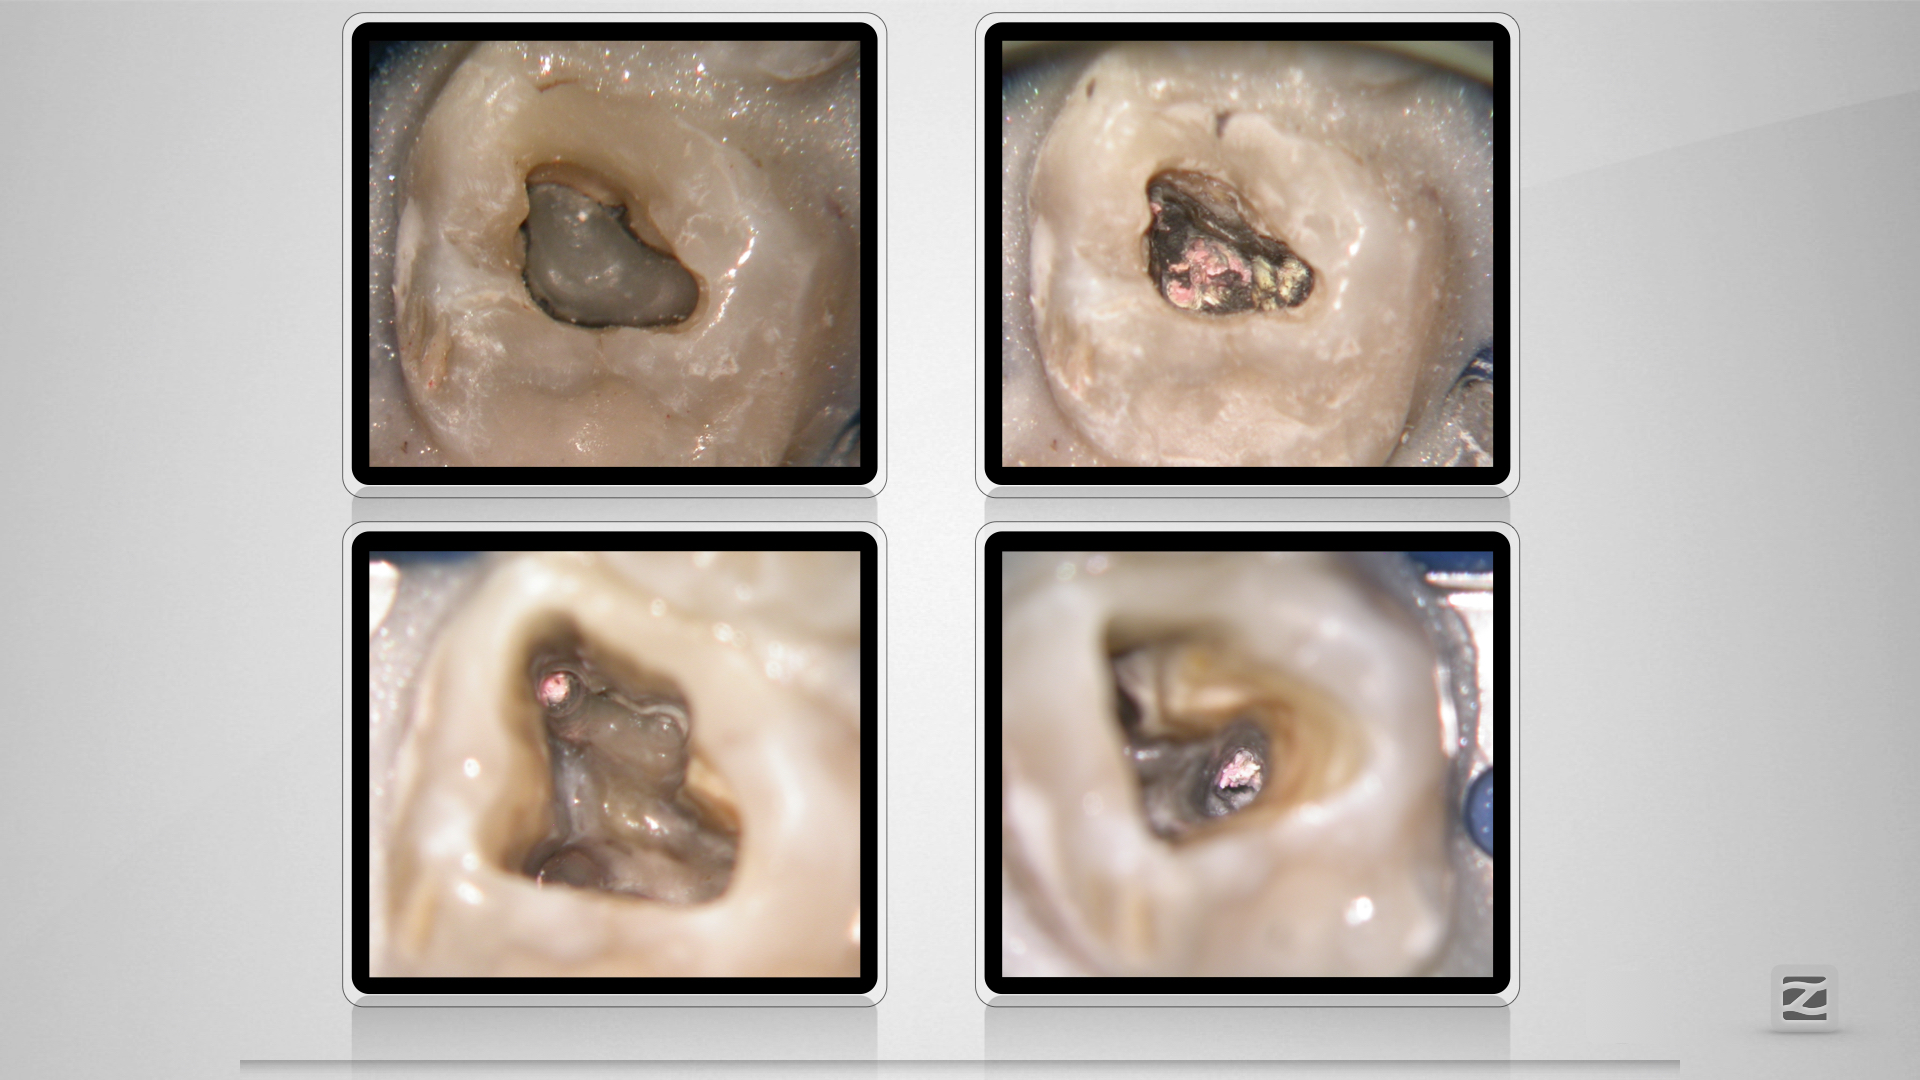

26D.005

Große Lyse